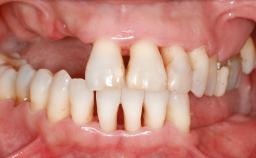

Ridge Preservation and Implant Placement for a Fixed Dental Prosthesis After a Car Accident

It is well known to clinicians that any removal of teeth will, over time, cause the dimensions of the alveolar ridge to be reduced by resorption of the bundle bone and by changes related to external modeling. This development is particularly evident in the crestal region with its thin buccal bone that consists of bundle bone almost entirely. The facial bone will rapidly resorb as blood supply from the periodontal ligament gets disrupted (Araújo and Lindhe 2005). There is no reason why traumatic tooth loss should not have the same consequences. It takes more than achieving implant osseointegration for a treatment outcome to be considered successful. No deficiency of bone or soft tissue is acceptable when an ideal esthetic outcome is the goal. Several articles (Sanz and coworkers 2011; Vignoletti and coworkers 2011) have reported on techniques of improving the alveolar ridge for implant treatment, notably focusing on protecting tissues from resorption.

# of Teeth 6

# of Implants 4

Bone Volume Horizontally and vertically sufficient Horizontally deficient Deficient vertically or deficient vertically AND horizontally

Defining Characteristics More than three missing teeth to be replaced with an implant-borne prosthesis or prostheses

Bone Volume Deficient vertically or deficient vertically AND horizontally